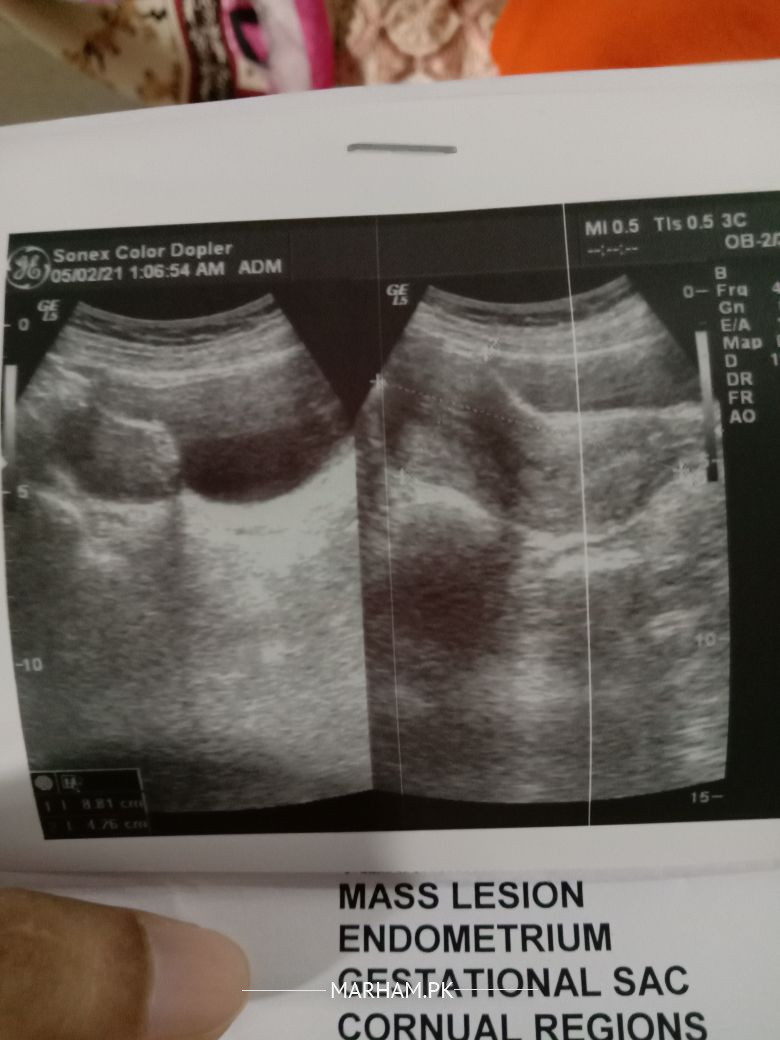

hi dr i have send my report and book video consultation

report